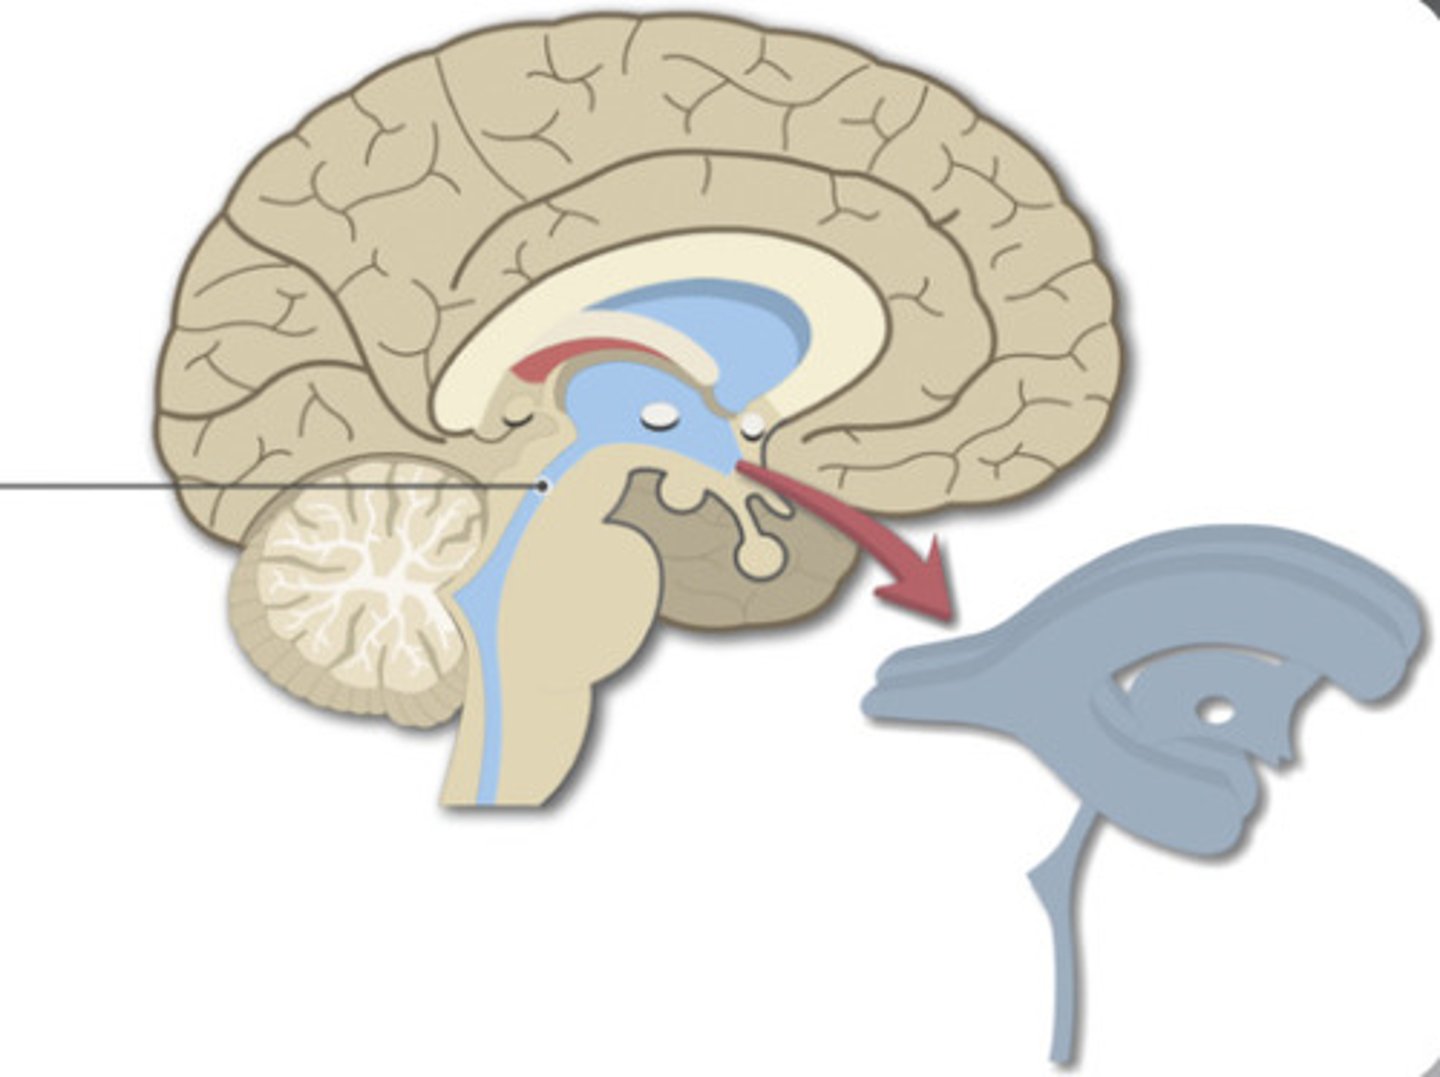

Lateral Ventricle

Third Ventricle

Fourth Ventricle

Cerebral Aqueduct

Sheep Lateral Ventricle

-produces and contains cerebrospinal fluid

Sheep Third Ventricle

sheep 4th ventricle